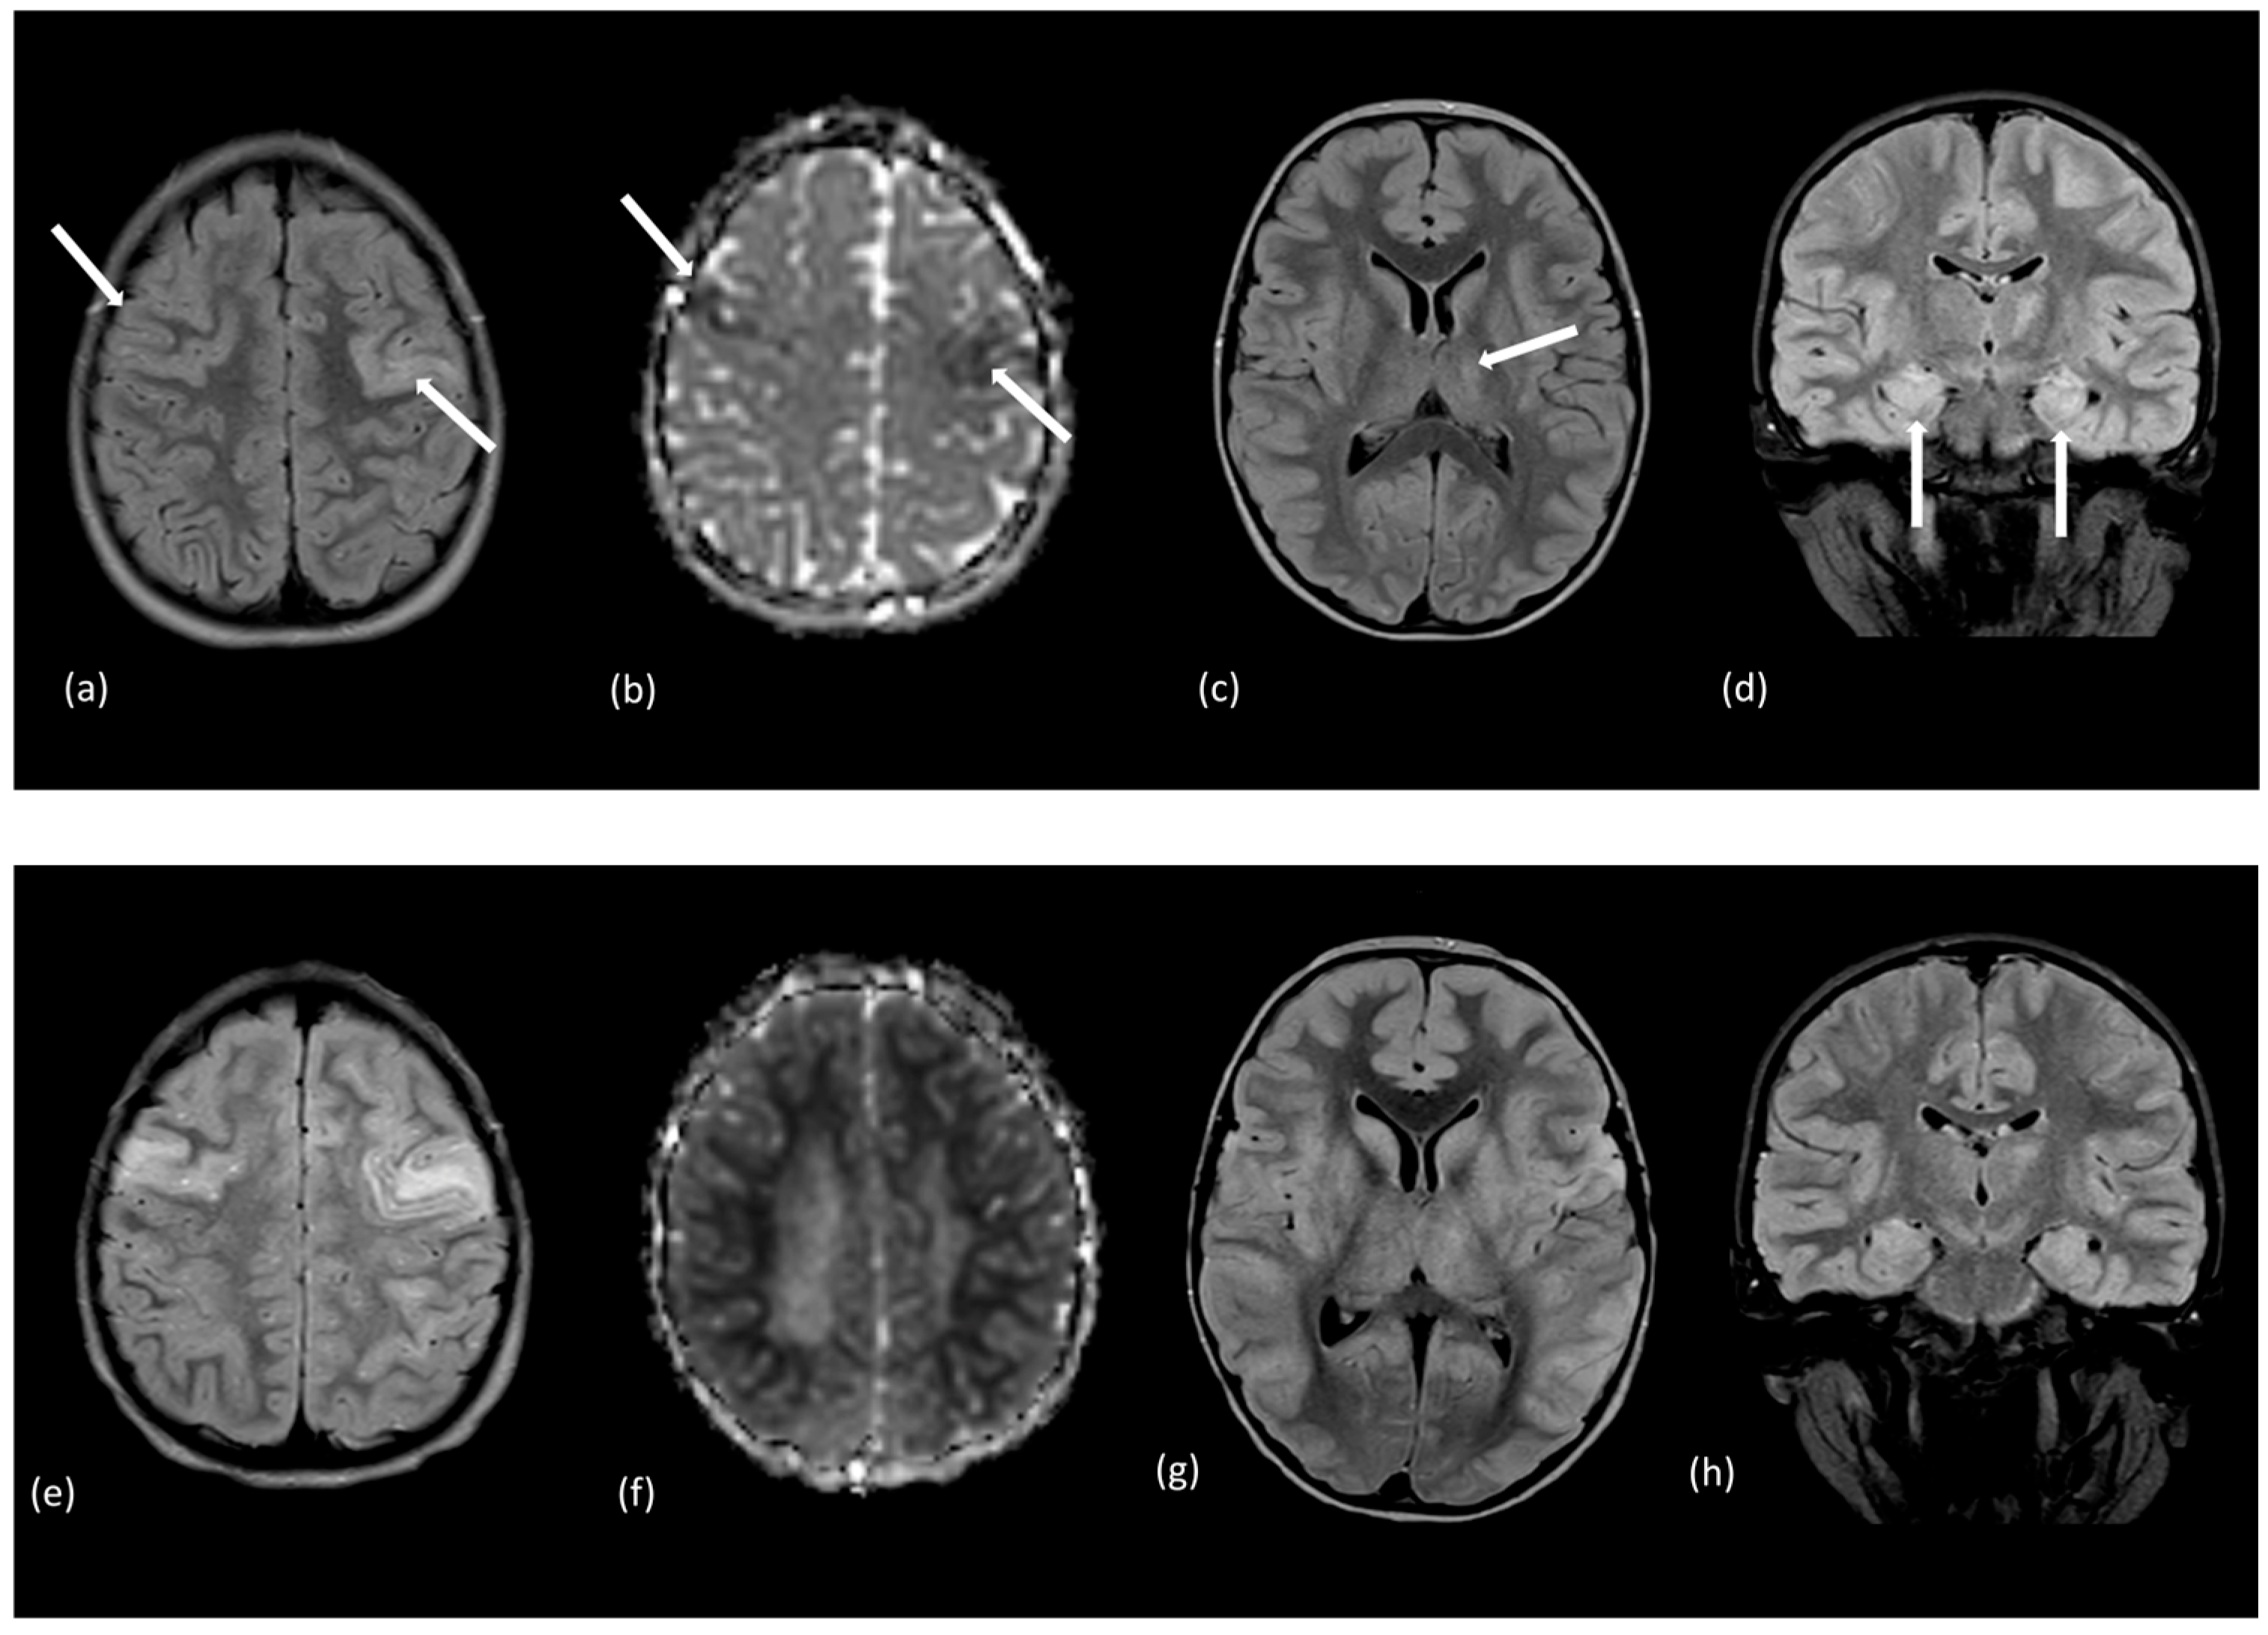

- de Bruijn, M.; Bruijstens, A.L.; Bastiaansen, A.E.M.; van Sonderen, A.; Schreurs, M.W.J.; Sillevis Smitt, P.A.E.; Hintzen, R.Q.; Neuteboom, R.F.; Titulaer, M.J.; Group, C.S. Pediatric autoimmune encephalitis: Recognition and diagnosis. Neurol. Neuroimmunol. Neuroinflamm. 2020, 7, 130–134. [Google Scholar] [CrossRef]

- Cellucci, T.; Van Mater, H.; Graus, F.; Muscal, E.; Gallentine, W.; Klein-Gitelman, M.S.; Benseler, S.M.; Frankovich, J.; Gorman, M.P.; Van Haren, K.; et al. Clinical approach to the diagnosis of autoimmune encephalitis in the pediatric patient. Neurol. Neuroimmunol. Neuroinflamm. 2020, 7, e663. [Google Scholar] [CrossRef]

- Gombolay, G.; Brenton, J.N.; Yang, J.H.; Stredny, C.M.; Kammeyer, R.; Otten, C.E.; Vu, N.; Santoro, J.D.; Robles-Lopez, K.; Christiana, A.; et al. MRI Features and Their Association With Outcomes in Children With Anti-NMDA Receptor Encephalitis. Neurol. Neuroimmunol. Neuroinflamm. 2023, 10, e200130. [Google Scholar] [CrossRef]

- Hou, C.; Li, X.; Zeng, Y.; Gao, Y.; Wu, W.; Zhu, H.; Zhang, Y.; Wu, W.; Tian, Y.; Zheng, K.; et al. Brain magnetic resonance imaging as predictors in pediatric anti-N-methyl-D-aspartate receptor encephalitis. Mult. Scler. Relat. Disord. 2024, 82, 105061. [Google Scholar] [CrossRef]

| AE | At presentation: >60% unremarkable | N/A | N/A | Depends on Antibody |

| At presentation: <40% with findings | NMDAR: all lobes, cortical, subcortical, basal ganglia, infratentorial | Meningeal | ||